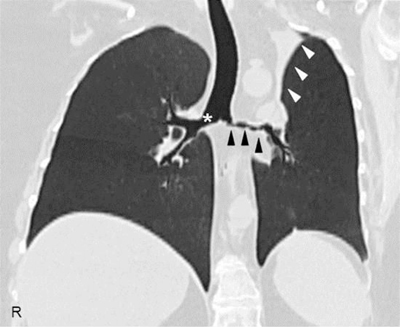

A 45-year-old female came to our attention with a six-month history of ulcerative mass in her right breast. Definitive pathology on breast lesion (Figure 1) documented the presence of a granulomatous mastitis with necrotic foci (asterisk), giant multinucleated cells (circles), and normal breast ducts in transversal (arrow) and longitudinal section (arrowheads) trapped by neutrophilic-eosinophilic infiltrate. Pathologist found no signs of malignant lesions. During the following months, the patient developed worsening cough, shortness of breath, nasal obstruction with hematic discharge, and hearing loss. Chest computed tomography (Figure 2) showed marked wall thickening of the right main bronchus (asterisk), stenosis of the left main bronchus (black arrowheads), and segmental atelectasis in the upper lobe of the left lung (white arrowheads). Paranasal sinuses computed tomography (Figure 3) showed a perforation of the nasal septum (asterisks), absence of the anterior half of the left inferior turbinate (white arrows), and atrophy of the upper lateral cartilages (white arrowheads). Fiberoptic rhinopharyngoscopyscopy documented the presence of extensive crusting rhinitis. Blood tests revealed high levels of antineutrophilic cytoplasmic antibodies with cytoplasmic pattern (c-ANCA). These findings were consistent with diagnosis of granulomatosis with polyangiitis. The patient was put under oral prednisone 1 mg/kg daily and cyclophosphamide monthly pulse therapy, with progressive improvement of breast and nasal lesions. She has currently reached a clinically stable NYHA Class II and is treated with prednisone 15 mg daily, methotrexate 15 mg weekly, and n-acetilcysteine 600 mg daily. She needs periodic endoscopic dilatations of bronchial stenosis.

Figure 2

High-resolution computed tomography of the chest, coronal reconstruction, showing a marked wall thickening of the right main bronchus (asterisk), stenosis of the left main bronchus (black arrowheads), and segmental atelectasis in the upper lobe of the left lung (white arrowheads).